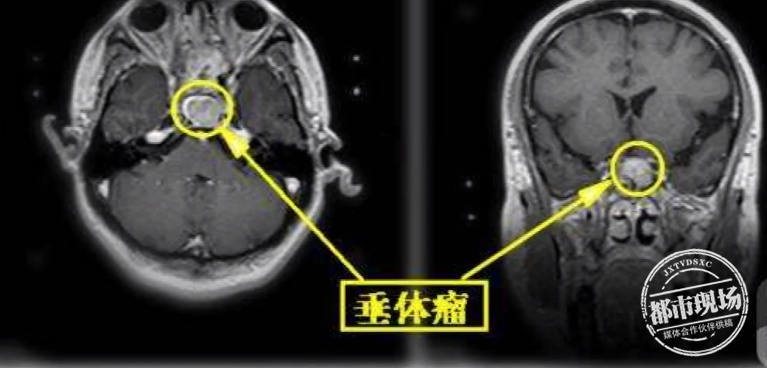

画面中,正在走路的这个高个子就是小明,他的头顶快碰到医院走廊的天花板了,同时他走路有一点迟缓,步子不稳。家属告诉医生,一年前,小明身高1米75,走路也正常,没想到,仅仅一年时间,他就蹿高了35厘米。感觉不太对劲的家属带着小明去了医院,在检查中,医生发现小明的脑部有一个巨大的垂体瘤。

医师 潘新发:我当时看到片子吓了一跳,脑部的肿瘤非常大,还有一个非常严重的并发症就是,肿瘤长大后,把中脑导水管的开口堵塞了,患者还有脑积水的症状,导致走路不稳。

医生介绍,垂体是重要的内分泌中枢,在临床上,垂体瘤超过4厘米就算是巨大瘤,而小明的肿瘤已达到了5厘米。在巨大肿瘤的影响下,他的生长激素分泌过度异常,指标超过正常值的60倍,所以才会在一年内蹿高35厘米。随后,医生通过微创手术,为小明切除了垂体瘤,目前已康复出院。